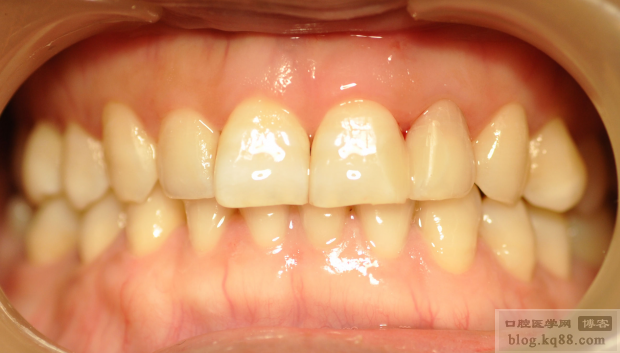

分層充填,其中背板我用的是GC的幻彩樹脂,中間用的KERR的樹脂

下面是充填完成還未進行調(diào)磨的照片

調(diào)磨拋光后,21的顏色稍微還有一點色差,自己不是很滿意,但是患者已經(jīng)很滿意